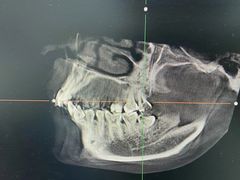

• 牙博士口腔品牌连锁(杨浦店)

• -牙博士口腔品牌连锁(杨浦店)

邵后 | 22-03-14